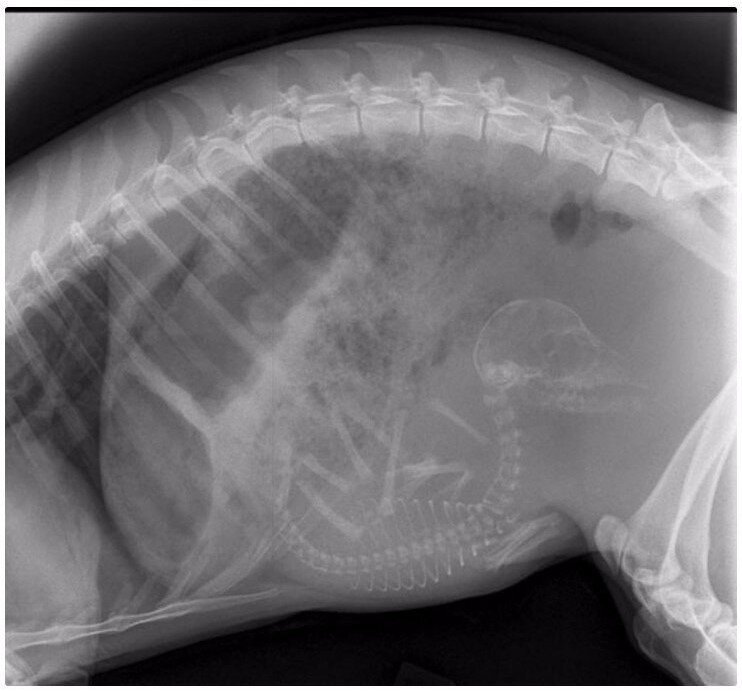

9. Беременная собака